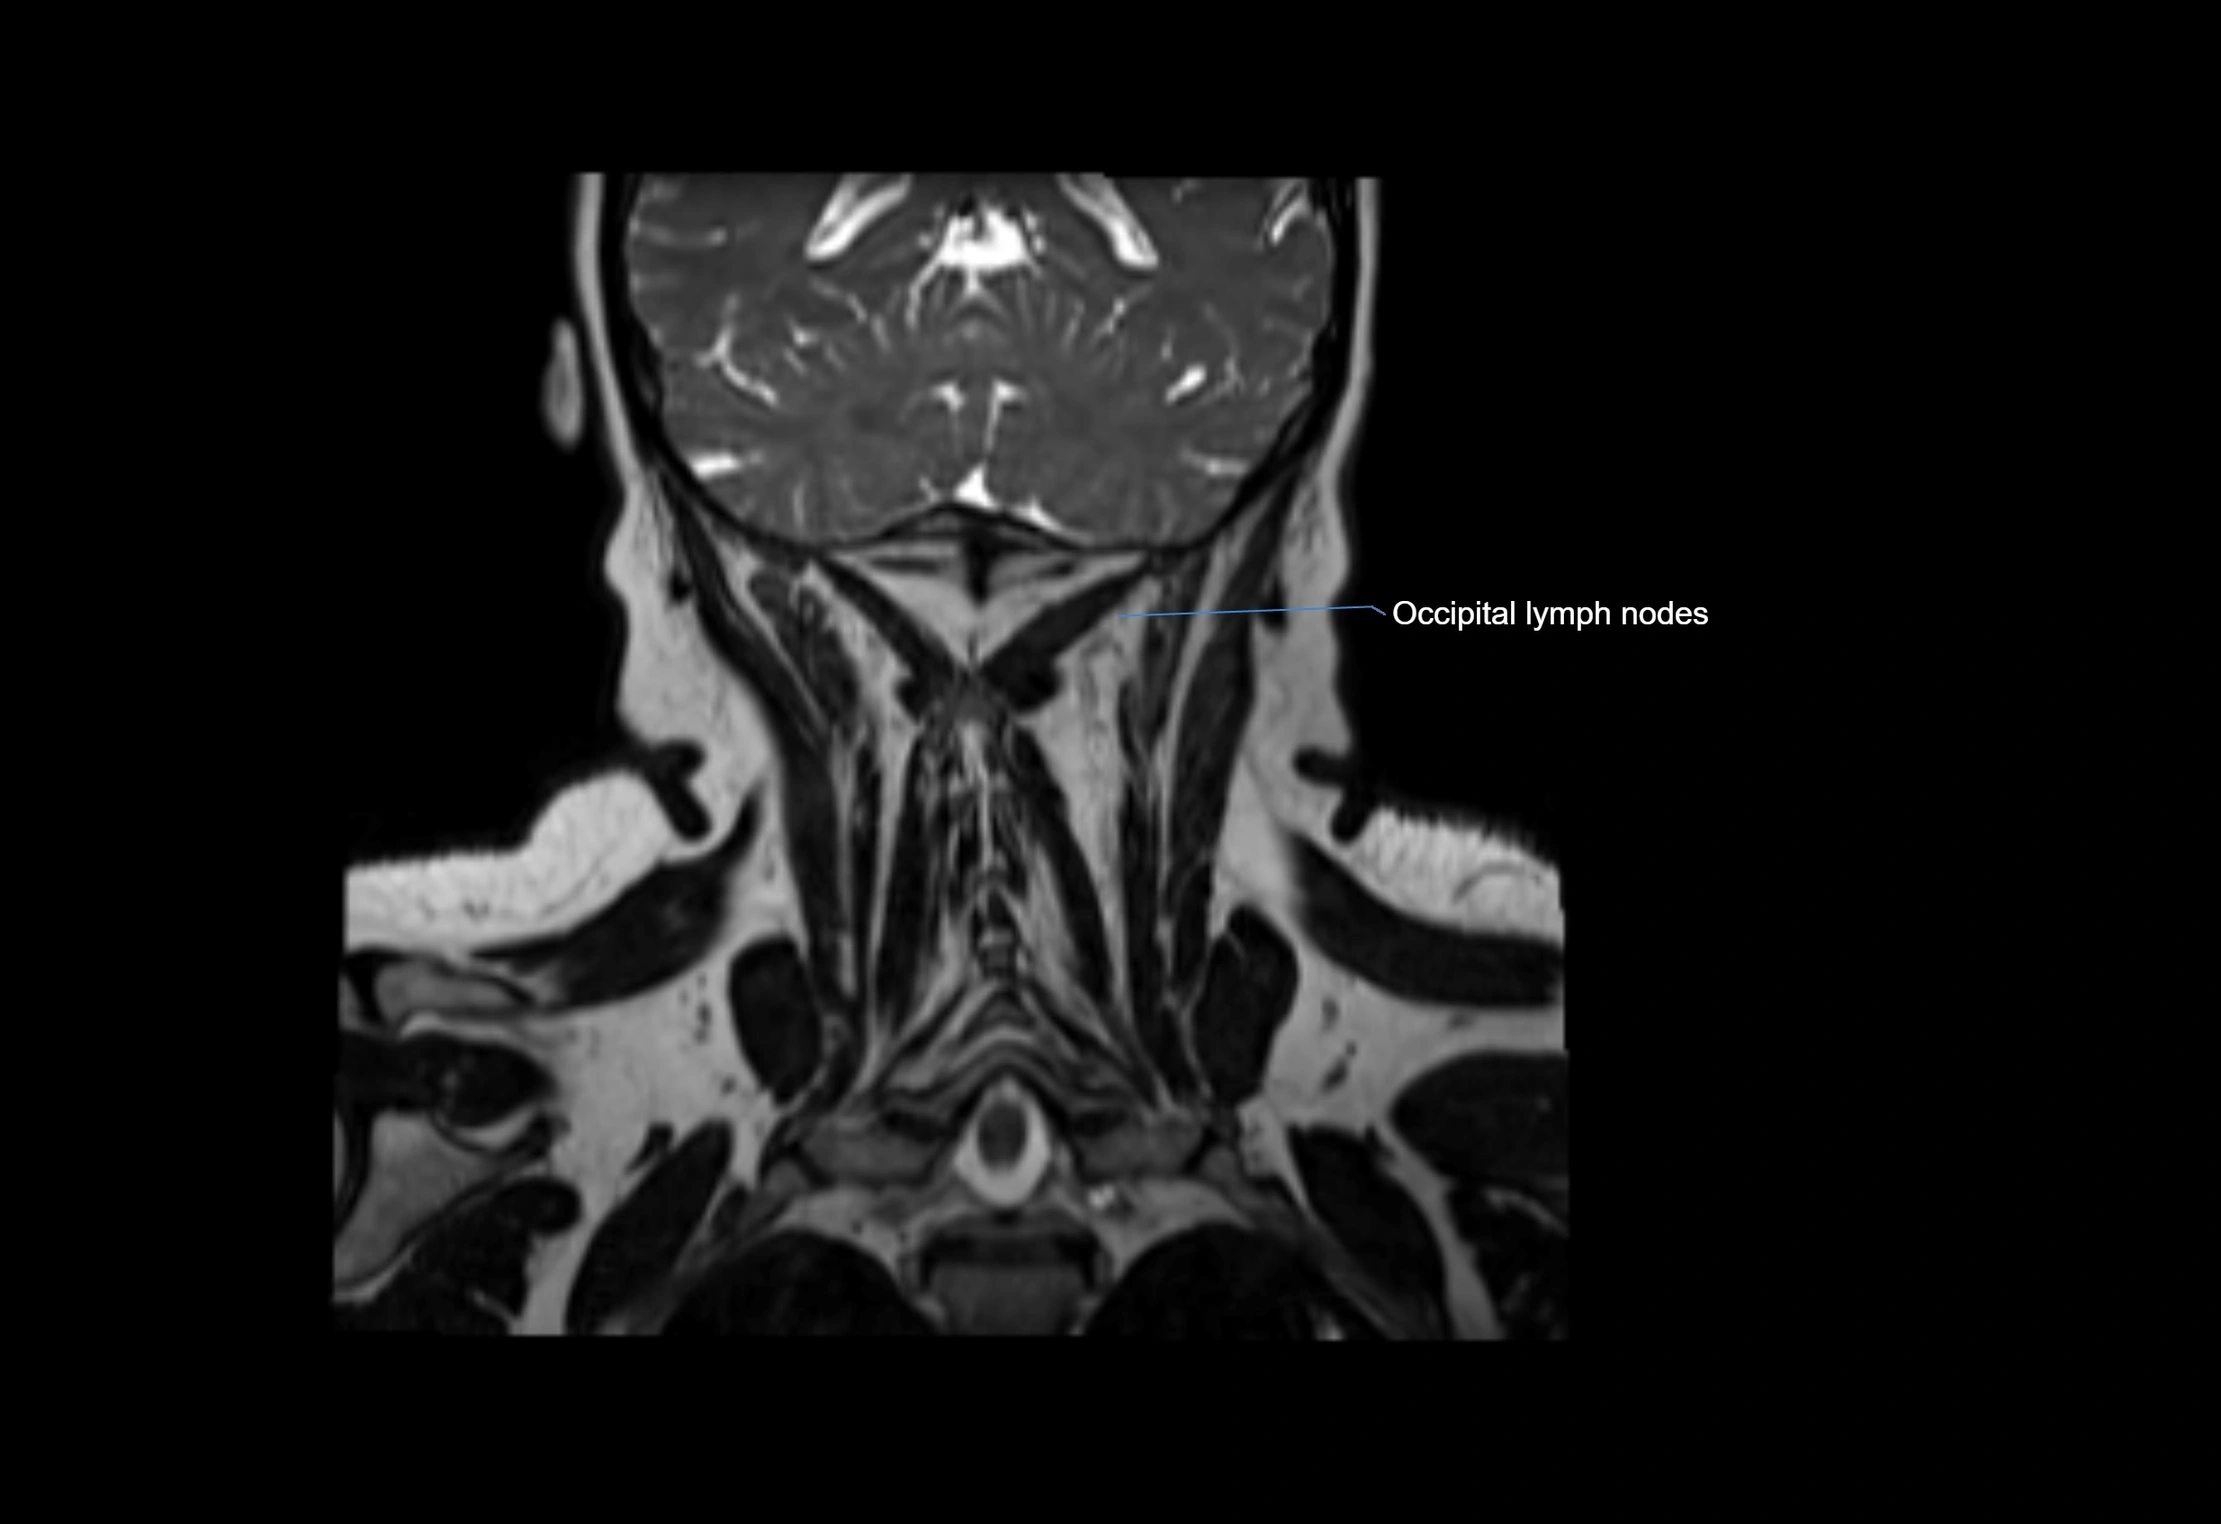

• Found along primary lymph node chains, including preauricular, submandibular, parotid, and occipital regions

• Embedded in subcutaneous fat or superficial fascia, often lateral or posterior to primary nodes

MRI Appearance

T2-weighted images:

• Nodes show intermediate signal, with surrounding fat bright

• Useful for detecting edema, inflammation, or infiltration

• Fatty hilum may appear slightly hyperintense relative to cortex

MRI images

image